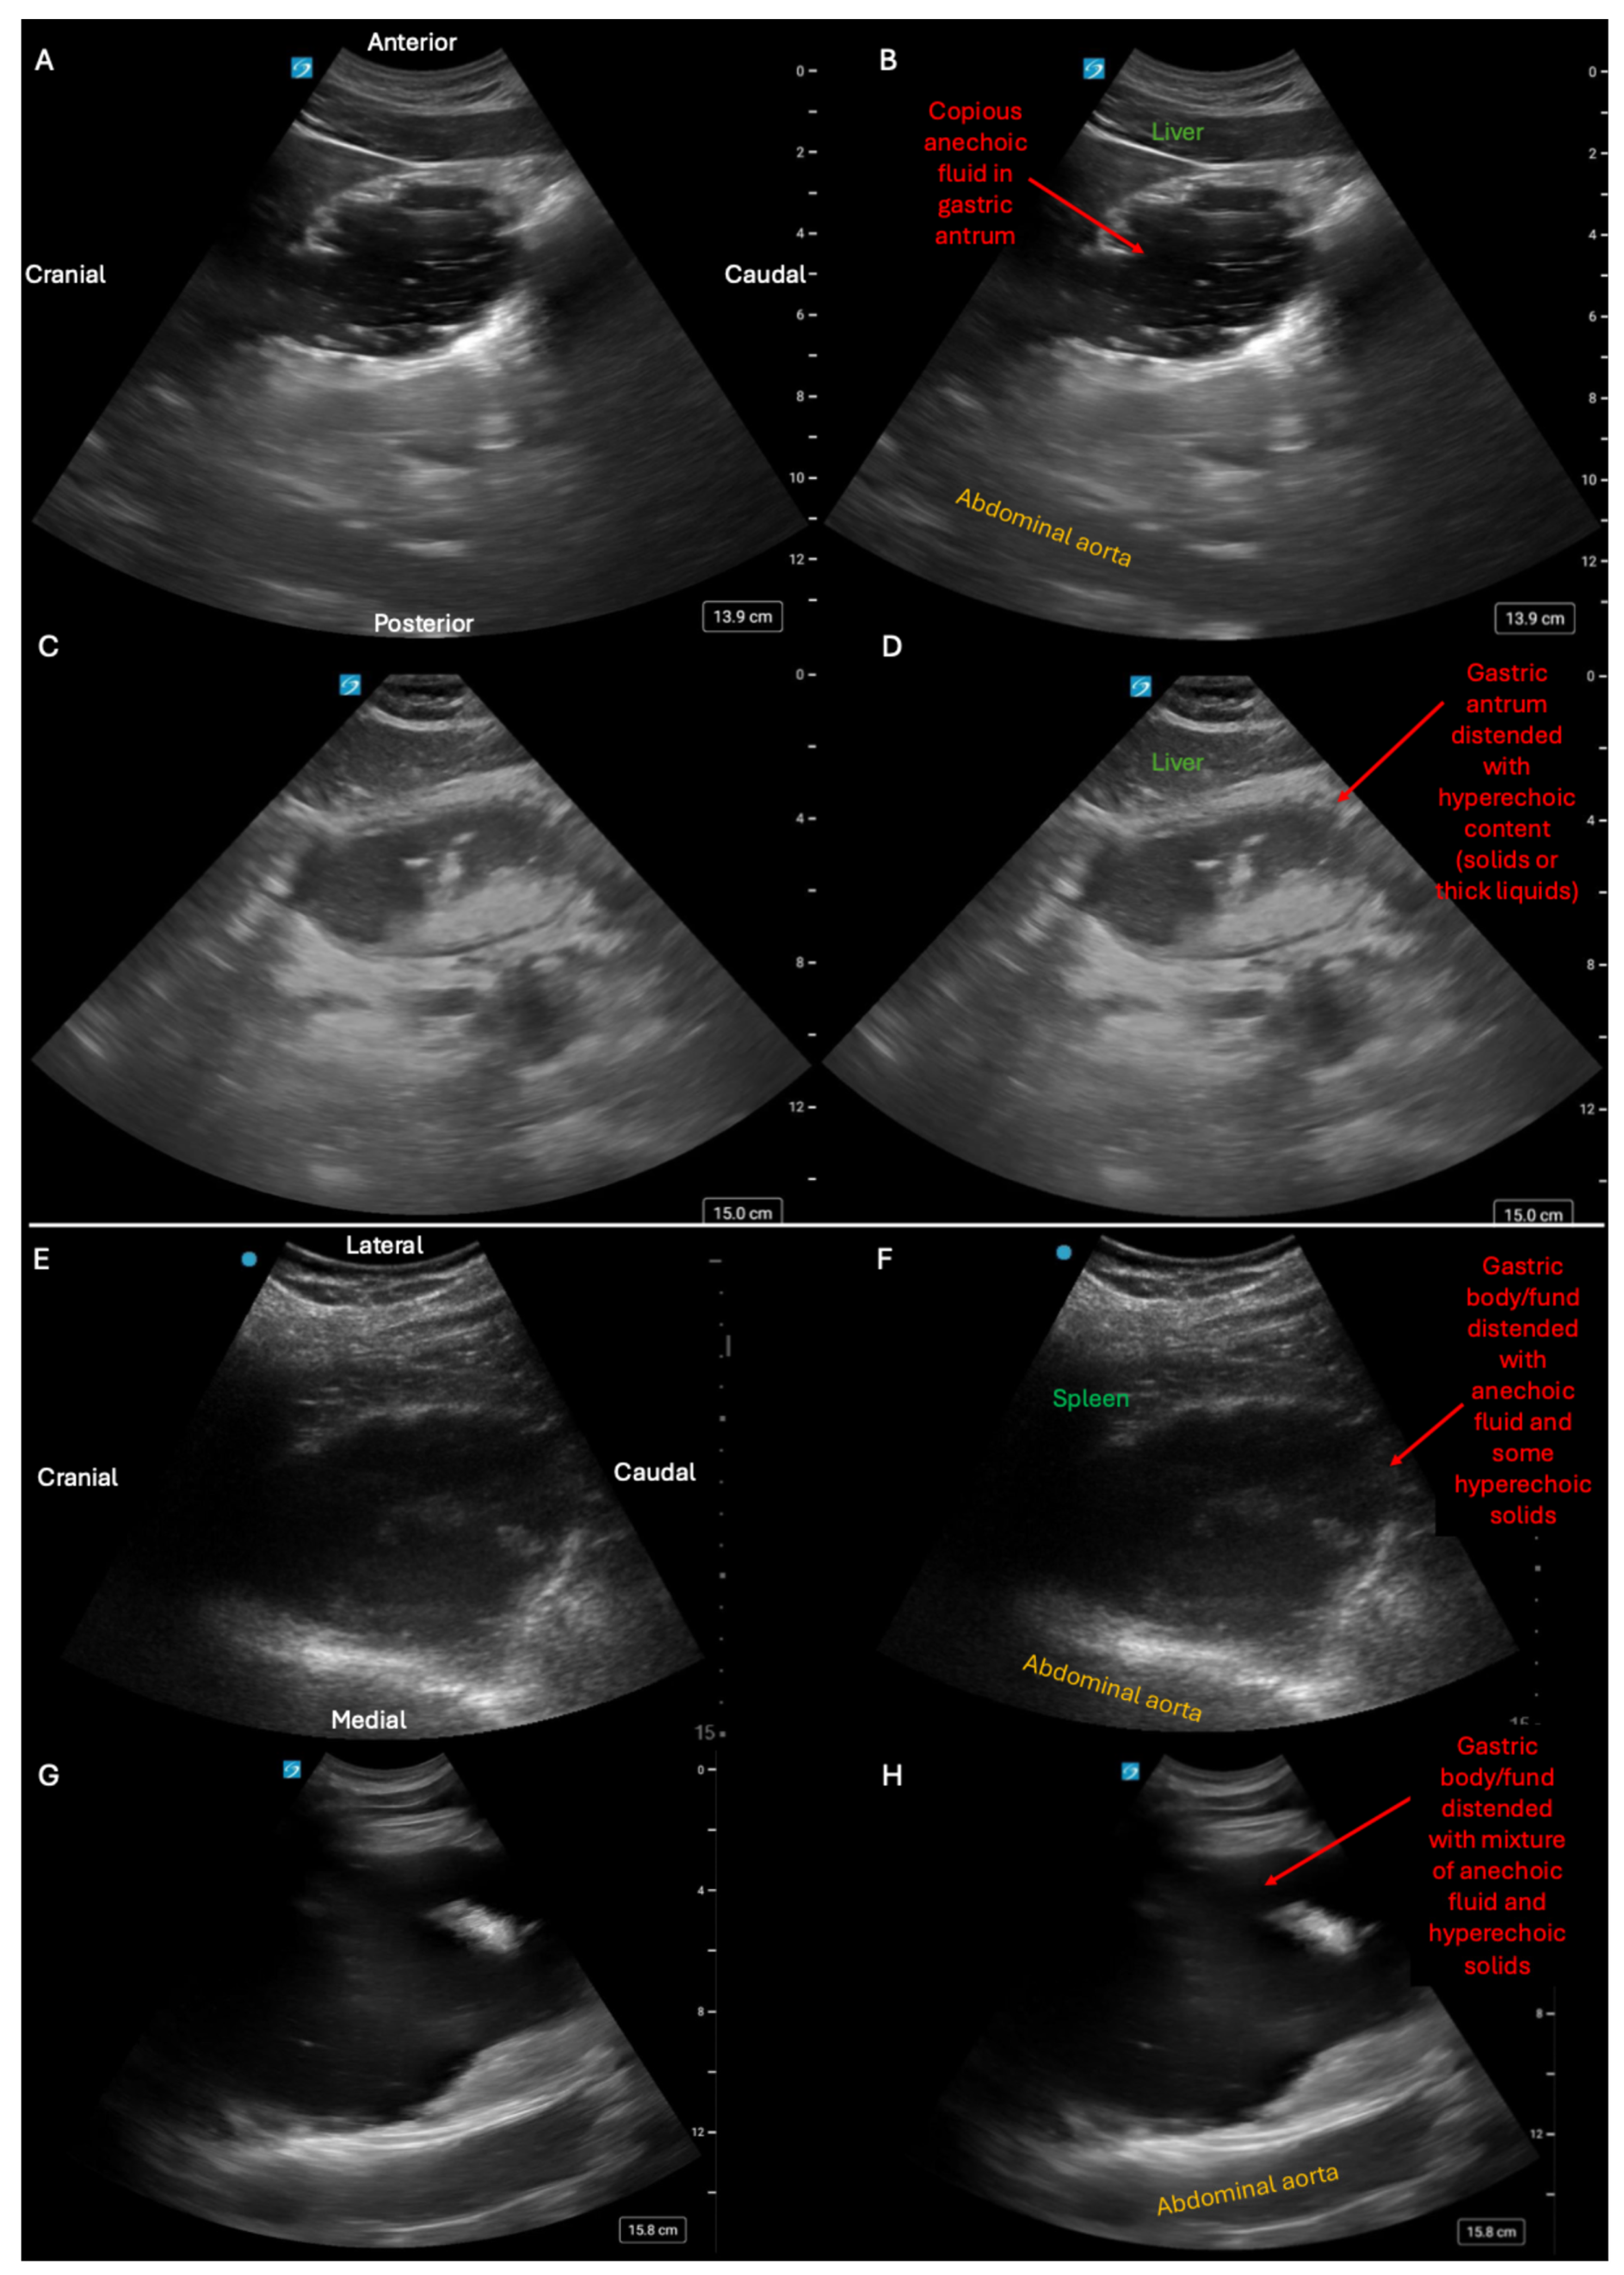

- Abramson, L.; Olive, J.K.; Lefler, B.; Wu, L.; Bowman, A.; Simpson, T.; Vatsaas, C.; Yanamadala, M.; Bronshteyn, Y.S. Point-of-care Ultrasound to Screen for Gastrointestinal Dysfunction: Image Acquisition and Interpretation. J. Vis. Exp. 2025, e68603. [Google Scholar] [CrossRef] [PubMed]

- Heinz, E.R.; Al-Qudsi, O.; Convissar, D.L.; David, M.D.; Dominguez, J.E.; Haskins, S.; Jelly, C.; Perlas, A.; Vincent, A.N.; Bronshteyn, Y.S. Gastric Point of Care Ultrasound in Adults: Image Acquisition and Interpretation. J. Vis. Exp. 2023, e65707. [Google Scholar] [CrossRef]